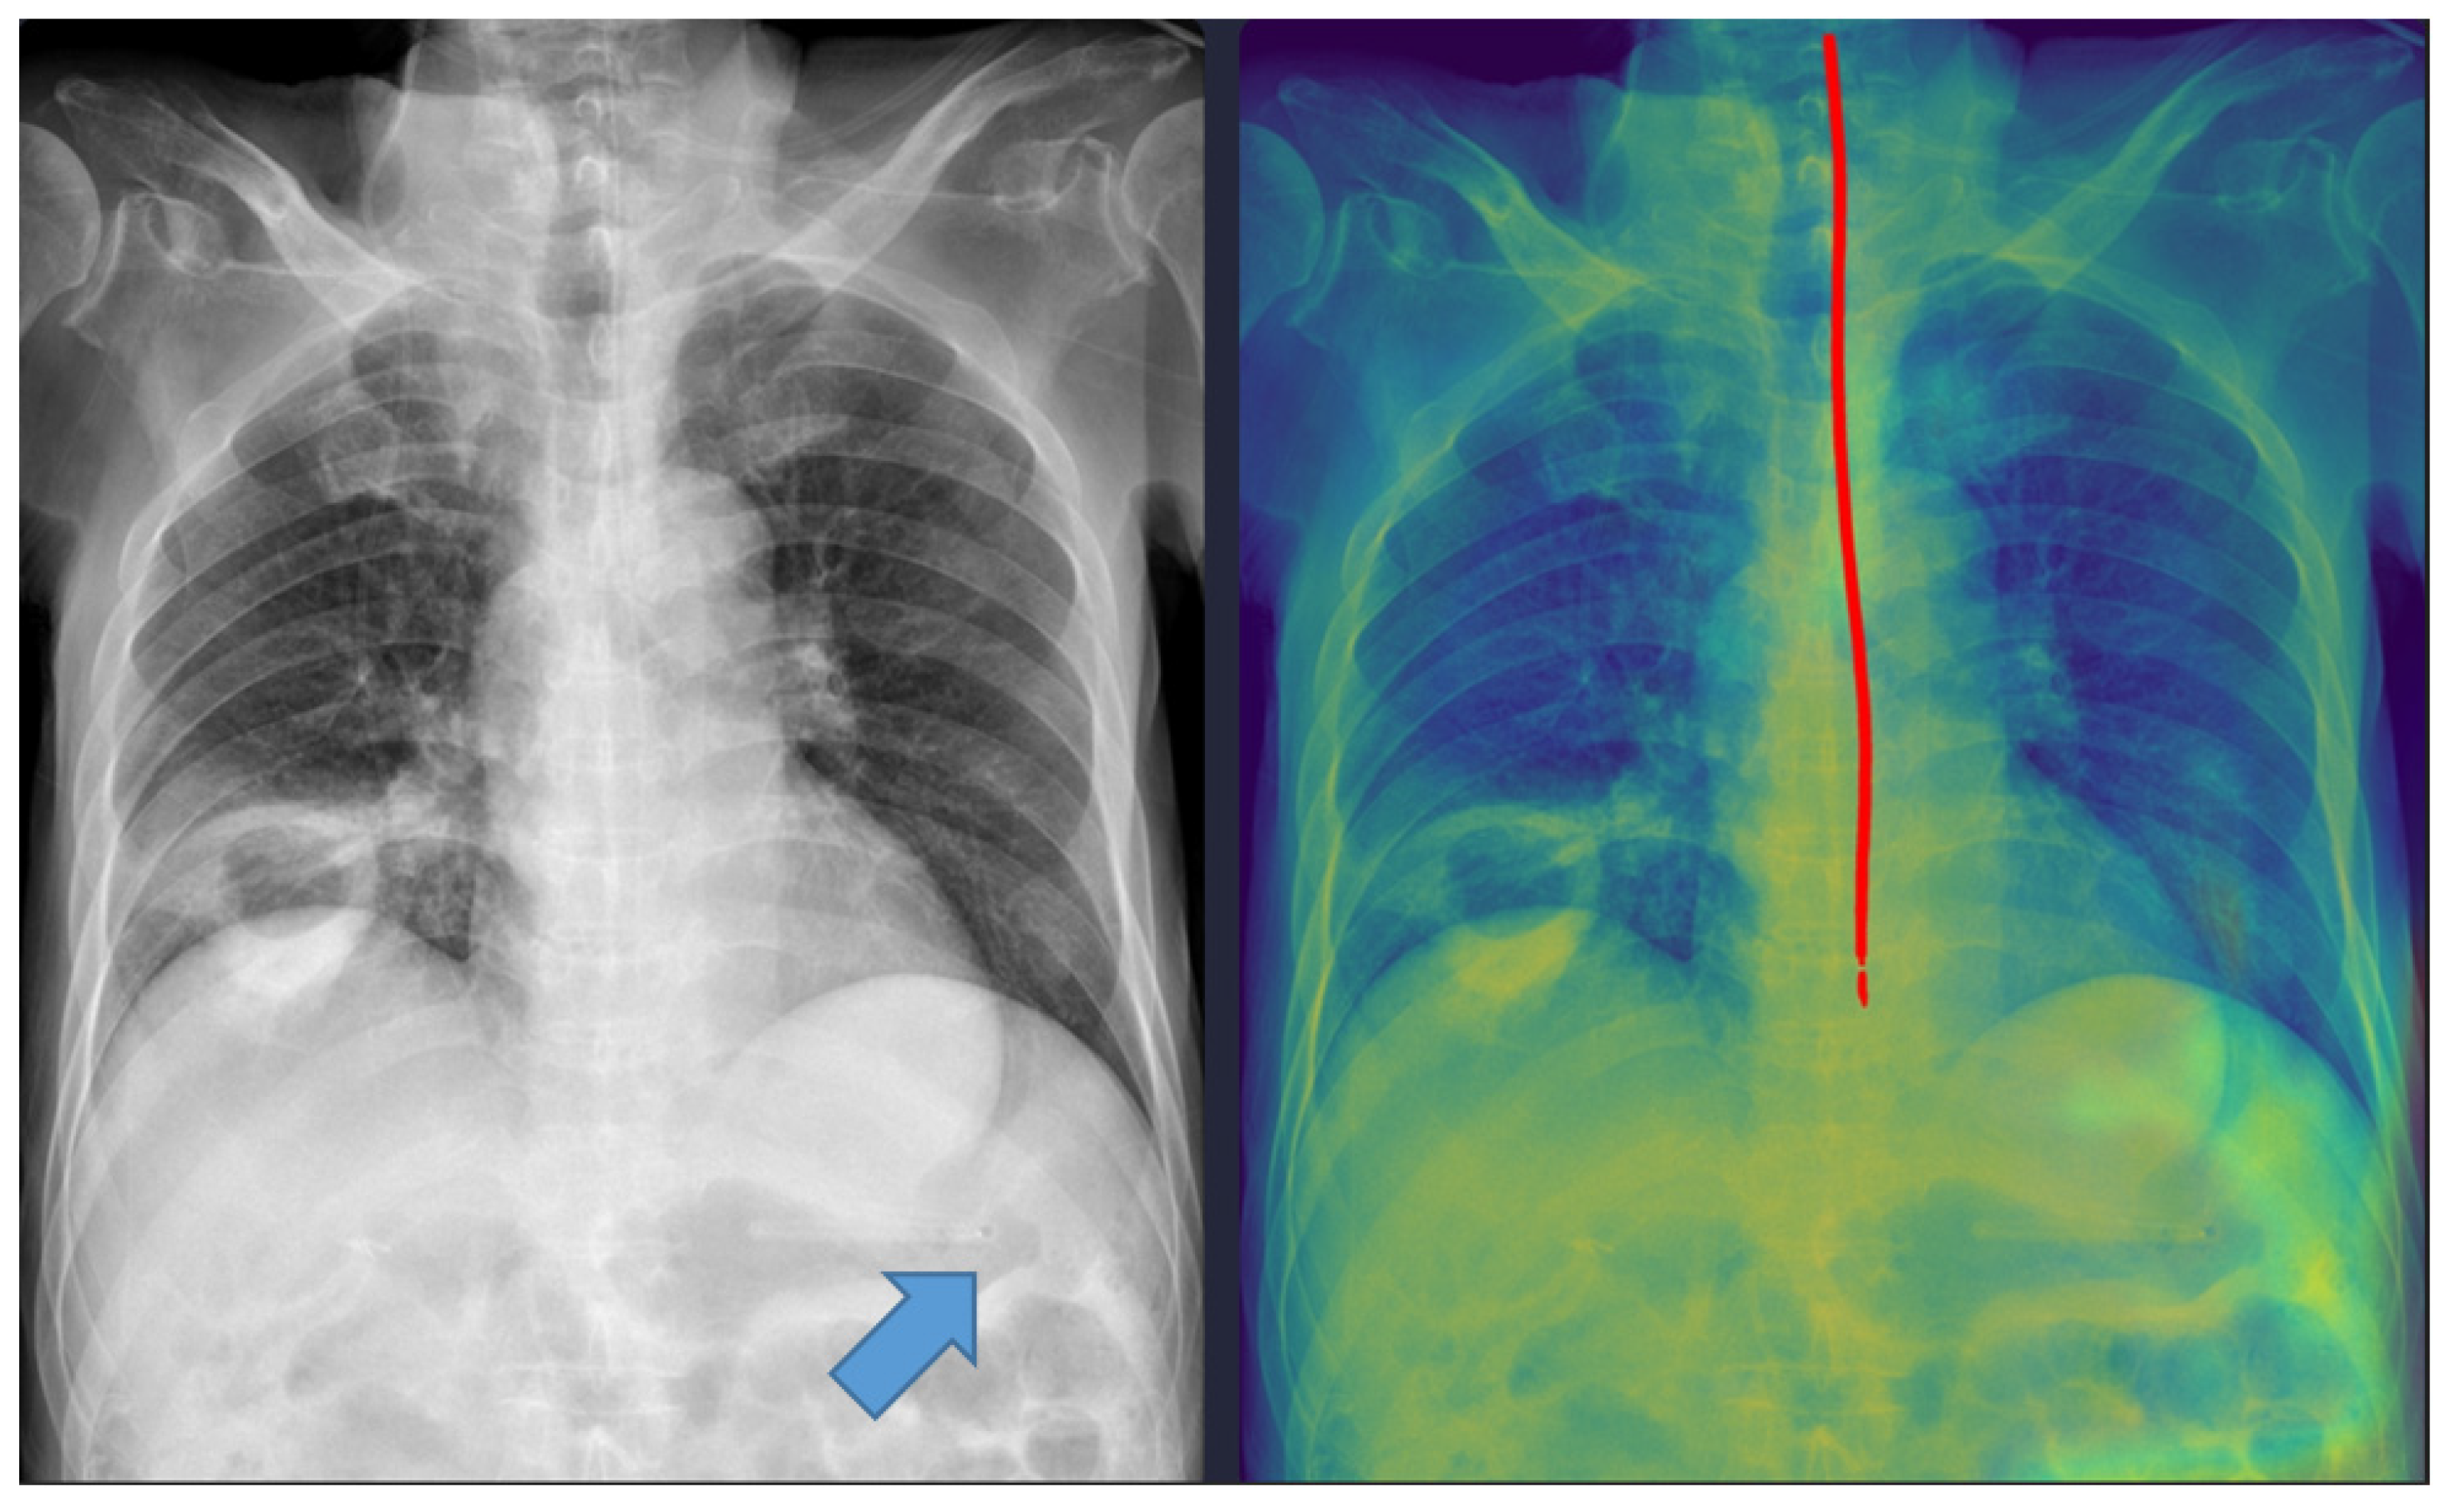

Representative examples of misclassified cases are shown in Figure 2 and Figure 3. The most critical failure involved an NG tube coiled at the indicated site in Figure 2, which suggested incomplete placement and a significant safety risk. The DL model misclassified this case as ‘complete’ based solely on the position of the tip projected below the gastroesophageal junction. Technically, this false-positive classification was highly likely due to the scarcity of such complex, coiled morphological features in the training dataset. While the segmentation module correctly identified the general tube structure, the dual-stage model failed to recognize this pronounced looping or coiling as an immediate risk factor, resulting in the classification module overriding the critical incomplete placement status. This finding identifies a crucial, previously unanticipated failure mode in the model’s design and carries substantial clinical significance, as initiating feeding through a coiled tube presents a high risk of aspiration pneumonia. Moving forward, efforts must focus on incorporating a greater diversity of these rare, yet clinically critical, coiled cases into the dataset to enhance the robustness of the tube segmentation process, thereby ensuring improved and safer clinical implementation. In Figure 3, the DL model failed to draw the entire trajectory of the NG tube and misclassified a complete case as incomplete. A representative example of a correctly classified case is shown in Figure 4. The tip of the NG tube is placed under the gastroesophageal junction and is safe to feed. Because most cases were correctly positioned (=95%), prevalence bias likely inflated the AC1 coefficient, and κ was lower despite near-identical classifications. Future studies should include more incomplete cases to obtain stable reliability estimates [12]. Prevalence-adjusted bias-adjusted kappa (PABAK) estimates were also evaluated with bootstrapping confidence intervals [13]. The results of the agreement among physicians and the DL model are shown in Table 4. Cohen’s κ showed the smallest estimate of 0.644 (95% confidence interval (CI): 0.366–0.922), which increased when using PABAK (0.911 (95% CI: 0.812–0.967)) and Gwet’s AC1 coefficient (0.956 (95% CI: 0.907–0.991)).

Figure 3. A misclassified complete nasogastric tube case identified as incomplete by the model. The arrow indicates the tip of the nasogastric tube. The red line represents the trajectory of the nasogastric tube as identified by the deep learning model.

Figure 4. Correctly classified nasogastric tube case. The red line represents the trajectory of the nasogastric tube, and the blue dot indicates the tip of the nasogastric tube as identified by the deep learning model.